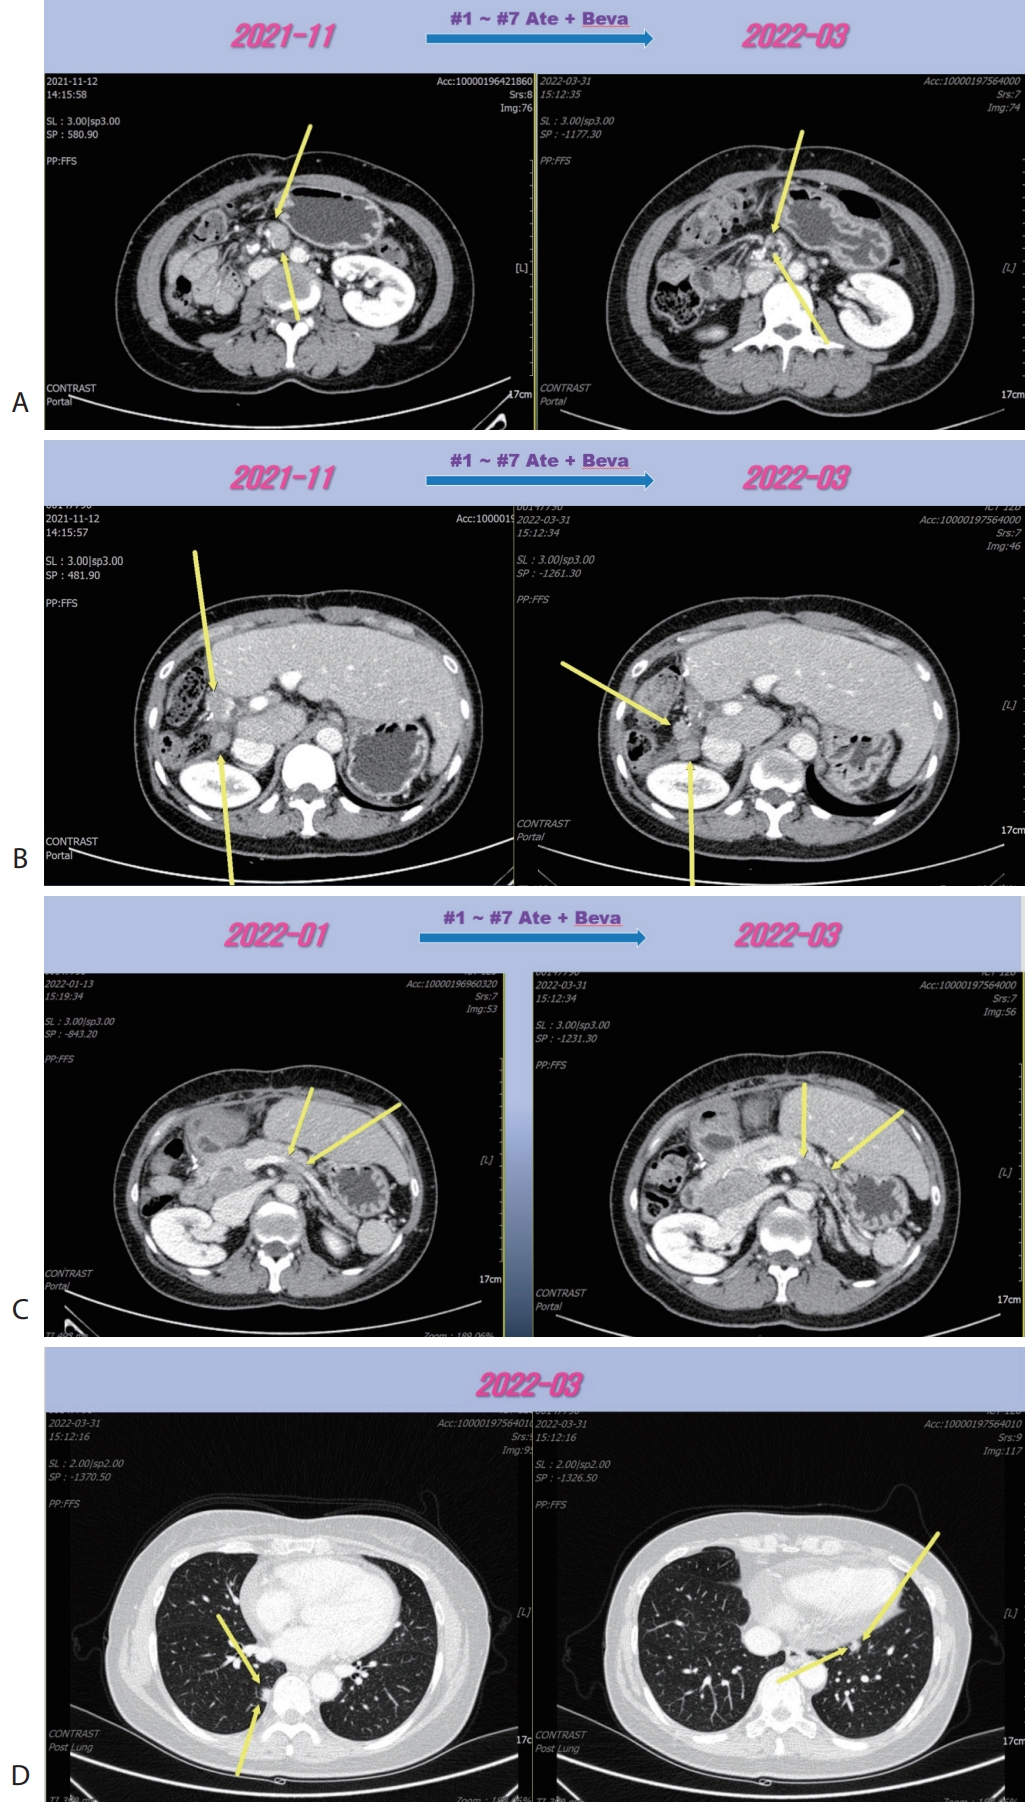

Figure 4.Liver CT scan (A, B) after 2nd line sorafenib therapy. New developed pelvic (A) and inguinal (B) lymph node metastasis were progressed after sorafenib therapy. CT, computed tomography.

Fig. 3D) and levels of AFP and PIVKA-II were normalized. We completed total thirty-two cycles of Ate+Beva for 2 years and we did not proceed further cycles of Ate+Beva because national medical insurance for Ate+Beva was terminated. At the time of stopping Ate+Beva, nearly CR state of tumor had been still maintained. However left inguinal & pelvic LN metastasis was recurred after 6 months from stopping Ate+Beva (

Fig. 4). Then the patient was treated with 2nd line sorafenib (Nexavar

®, 200 mg per dose; Bayer, Leverkusen, Germany) for 2 months, but LN metastasis was progressed (

Fig. 4). Then the patient was treated with 3rd line regorafenib (Stivarga